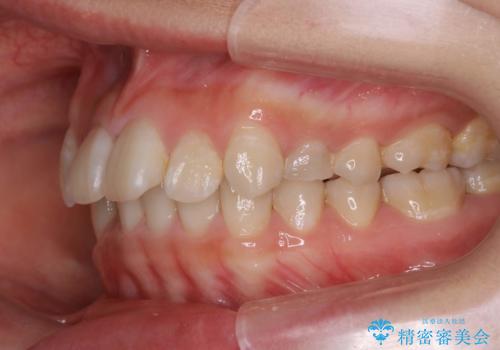

ハーフリンガル矯正 抜歯をして前歯を下げる

- ハーフリンガル

- 上顎の両側第1小臼歯抜歯による抜歯矯正を計画した。

上顎の抜歯により上の前歯の位置を大幅に後ろに下げることができます。

奥歯の位置関係など、様々な要素を加味し、適応を判断する必要があります。